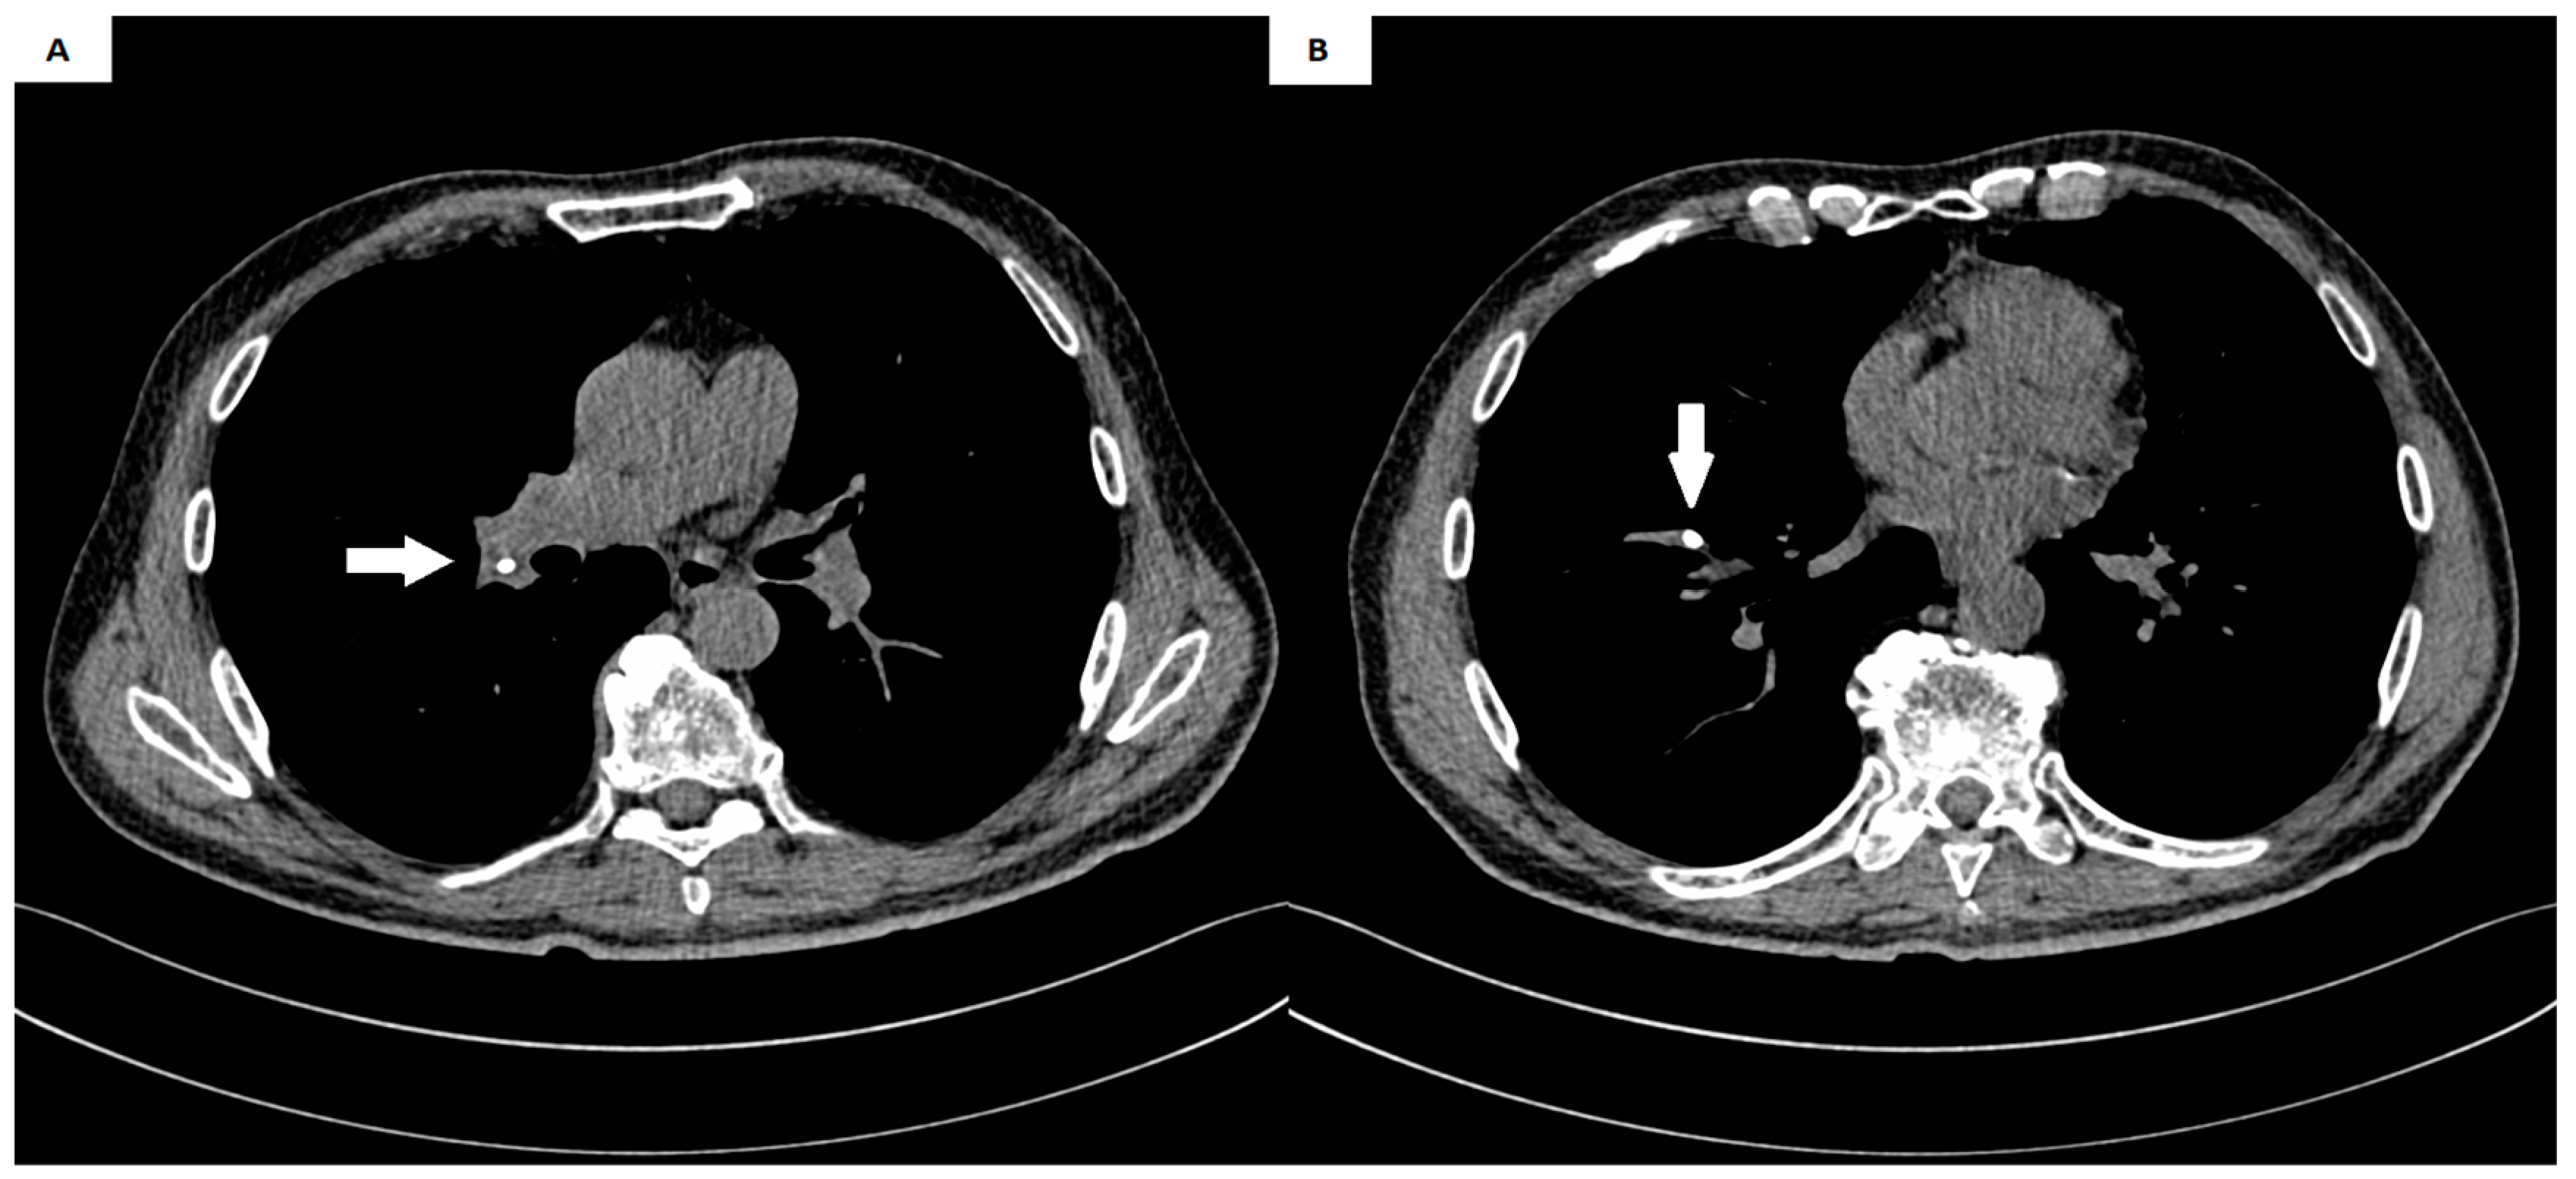

| Presented case | M | 67 | Gastric cancer | Cough, weakness, nausea, and heartburn | Right pulmonary artery | 8 | Thoracotomy |